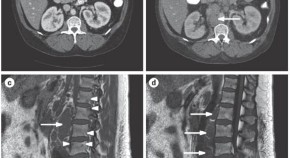

• This Case Study of a 14-year-old boy with juvenile-onset ankylosing spondylitis discusses the complexities of the nomenclature, classification, and diagnosis of the spondyloarthropathies in children, and how these matters have important implications for treatment.

• Rubén Burgos-Vargas

Case Study